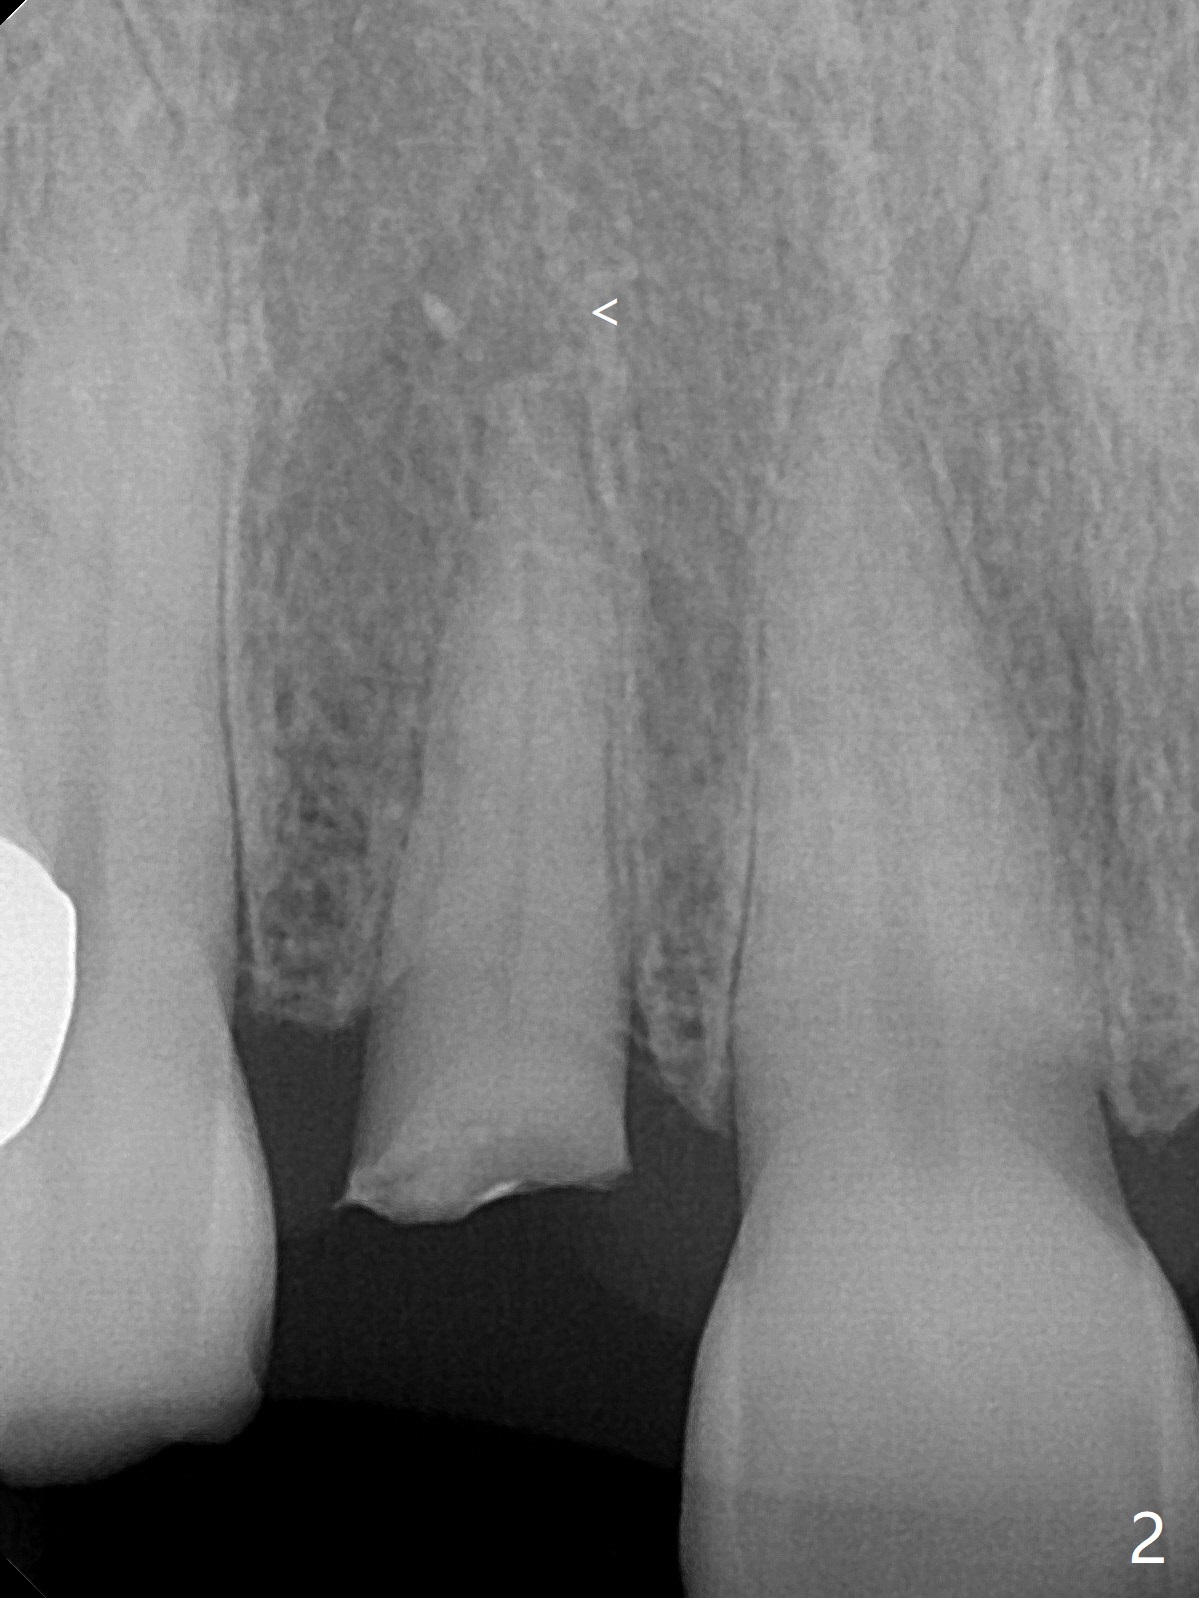

The rebonded crown at #7 debonds in a few days. There is deep anterior overbite and buccal concavity (Fig.1 *). The equigingival fracture (Fig.1,2) seems difficult to restore considering lack of posterior support (lower RPD in Fig.1). Buccal shield is tried in spite of the long root. It is not easy to tell whether the infected apex is removed due to the deep socket. In fact the apical buccal plate perforates because of use of surgical handpiece. Finally the buccal shied is removed. PA confirms the retained apex (Fig.3 *). The initial osteotomy with 1.5 mm drill in place is off trajectory (Fig.4). After adjustment of the trajectory of osteotomy (Fig.5), a 3x16(2) mm 1-piece implant is placed within normal limit (10-15 Ncm, Fig.6)). In fact bone graft is placed before (Fig.6,7 arrowhead; to repair apical buccal plate perforation) and after (Fig.6 *) implantation. The gingiva (including papillae) remains normal around the provisional 3 months postop (Fig.8). The bone graft becomes more organized 3 months postop (Fig.9), continues to do so 4.5 months postop (Fig.10) and becomes dense coronally 9 months post cementation (Fig.11: *).